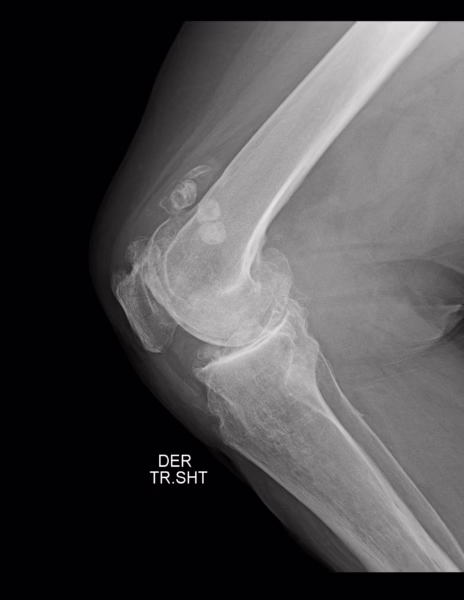

RADIOGRAFIA AP Y LATERAL DE RODILLAS.

Los tejidos blandos de ambas rodillas a nivel de grasa suprapatelar y periférica al articulación con presencia de imágenes radio pacas, redondeadas, irregulares, bien definidas, con centro sutilmente radiolúcido al resto de la periferia, de lado izquierdo miden desde 6.5 mm hasta 2.22 cm y de lado derecho desde 1.4 cm a 1.67 cm. Resto sin alteraciones.

Estructuras óseas; fémurs distal y tibias proximales, sin evidencia de lesiones líticas, blásticas o perdida de la contigüidad. Existen osteofitos marginales.

Rotulas, centrales, sin evidencia de lesiones líticas, blásticas o perdida de la contigüidad. Existen osteofitos marginales.

El espacio articular femorotibial, con disminución severa de su amplitud.

Espacio articular patelofemoral, con disminución severa de su amplitud.

Angulo femorotibial derecho de 173.6° e izquierdo de 174 °.

Angulo Muñiz derecho de 5° e izquierdo de 7.1°.

Índice de install-salvati derecho de 0.8 e izquierdo de 1.07.

EN EL PRESENTE ESTUDIO RADIOGRÁFICO, EXISTE GONARTROSIS SEVERA BILATERAL.

CALCIFICACIONES PERIARTICULARES EN TEJIDOS BLANDOS DE PREDOMINIO EN GRASA SUPRAPATELAR BILATERAL DE PREDOMINIO EN RODILLA IZQUIERDA.